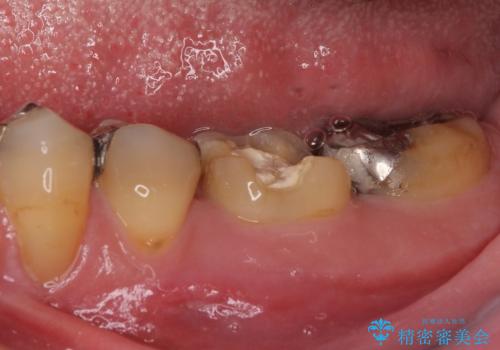

- 近医にてむし歯治療として根管治療を受けるも、痛みが全く改善しないとのことで来院された患者様です。

痛みが継続するため、「根管治療」と検索したところ、「ラバーダム」の重要性を知るところとなったようです。

根管治療を実施した後に、フルジルコニアクラウンにて補綴することとしました。